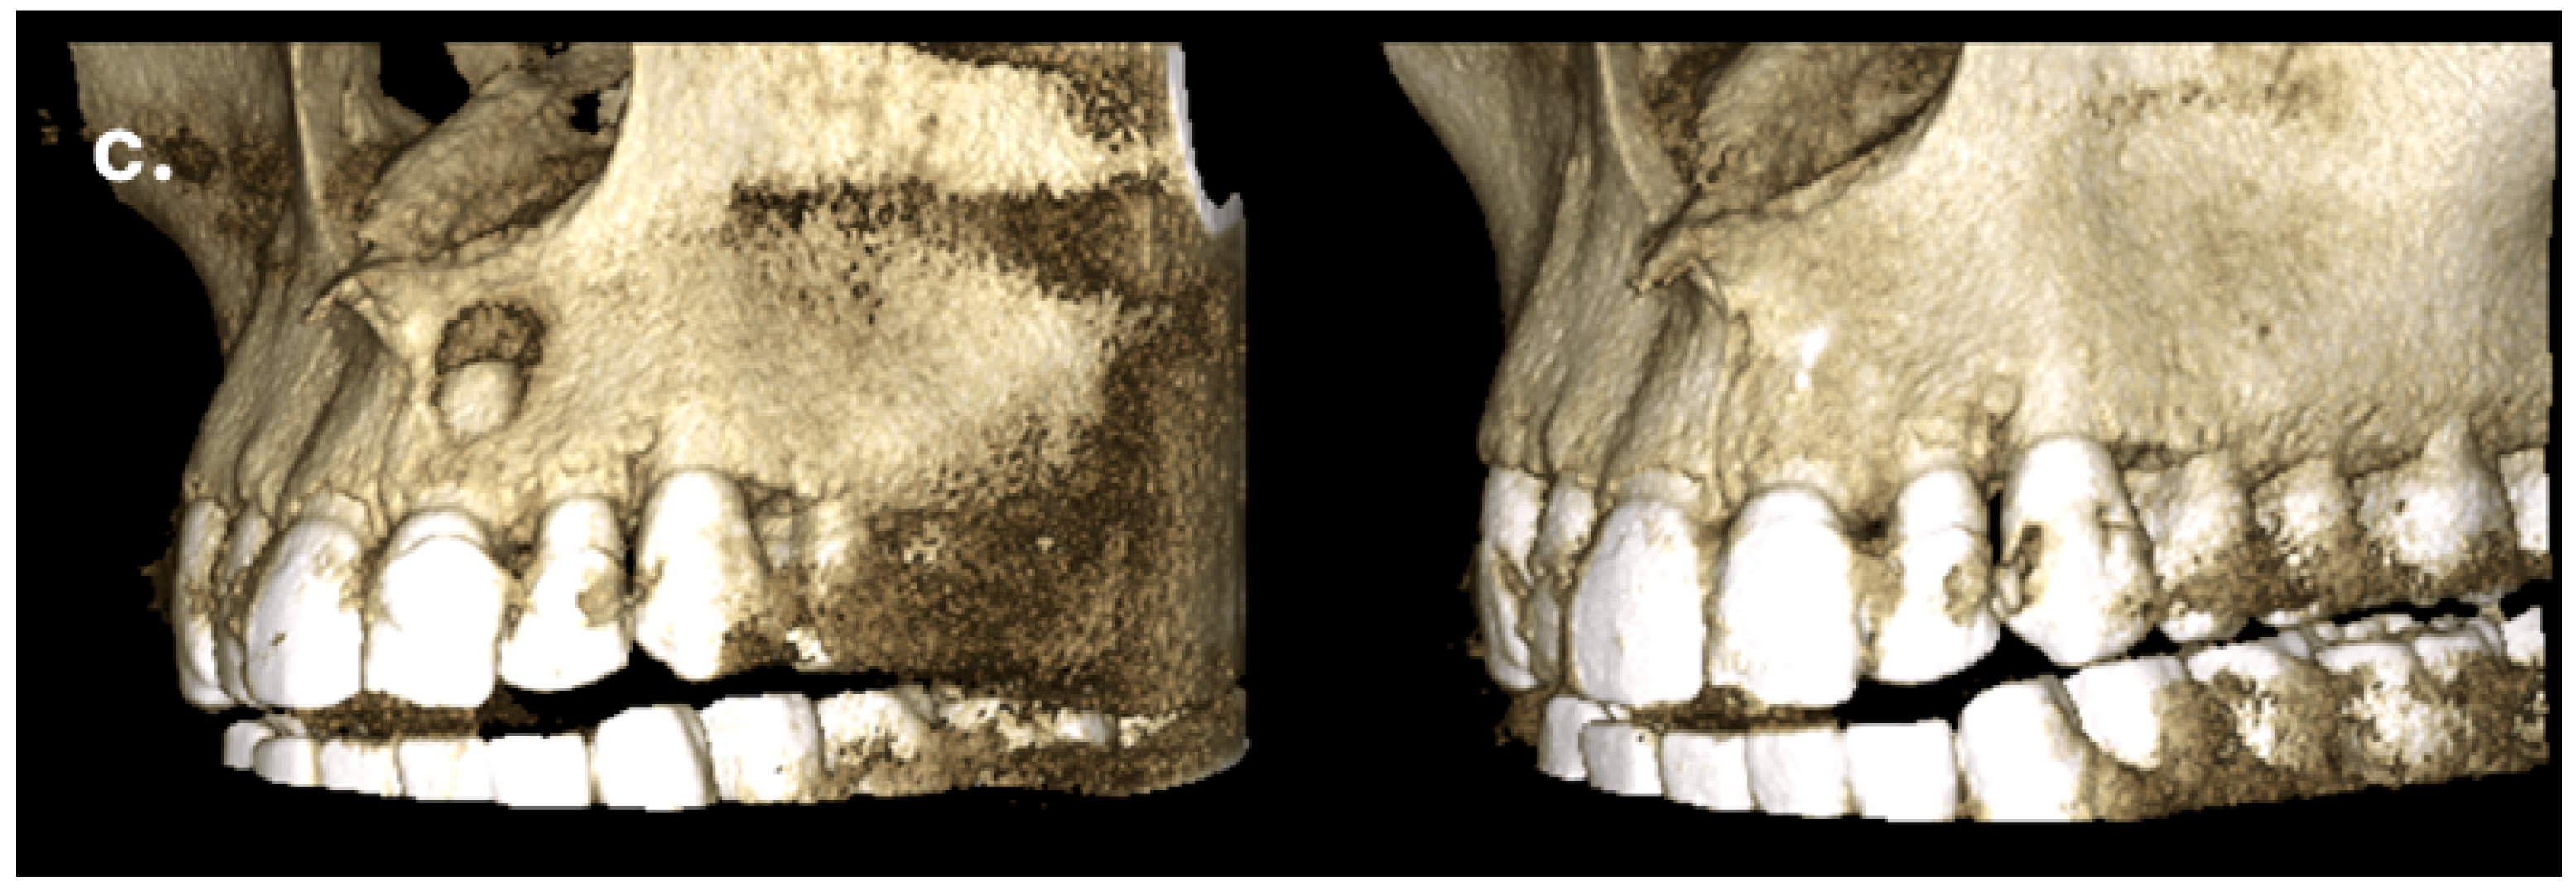

Figure 3. The labial bone fenestration is visible on the CBCT image (indicated by red arrows).

The CBCT scan revealed a labial cortical bone defect associated with tooth #21, measuring approximately 7 mm in diameter. The apical third of the root was uncovered by bone; an apical bone fenestration was present. The palatal cortical bone remained intact and was not affected by the periapical pathology (Figure 3). According to the CBCT Periapical Index (CBCTPAI), the lesion was classified as score 4 + D, indicating extensive periapical radiolucency with destruction of the cortical bone [9].

The patient returned for a follow-up visit two years later. The tooth was asymptomatic, and the radiograph showed no signs of periapical radiolucency (Figure 5a). The caries lesion on the mesial surface was treated. Eight months later, a new CBCT scan was performed by another dentist due to a traumatic injury on the right side of the jaw. Upon reviewing the scan, valuable diagnostic information became apparent, including complete restoration of the cortical bone, reestablishment of healthy periapical tissues, and the absence of any radiolucency around the apex of tooth #21. The CBCT PAI score was recorded as 0, indicating complete healing (Figure 5b,c).

Figure 5. Complete regeneration of the apical bone fenestration observed over a period of two years and eight months: (a) periapical radiograph showing resolution of the periapical radiolucency; (b) CBCT scan confirming re-establishment of the cortical bone and healthy periapical tissues; (c) the 3D reconstruction is included to illustrate the anatomical changes before and after treatment.